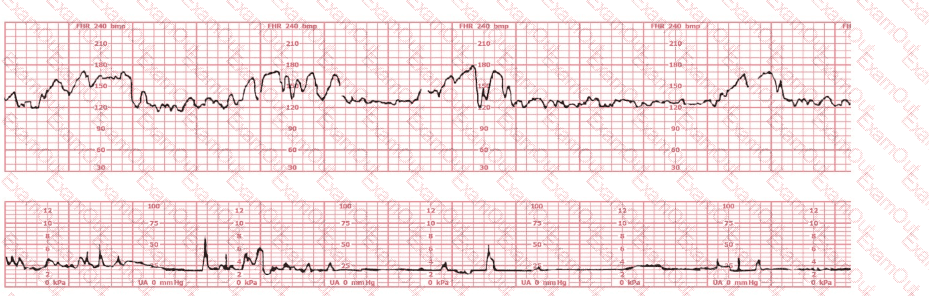

The fetal heart rate tracing shown demonstrates:

What is the appropriate interpretation of this tracing?